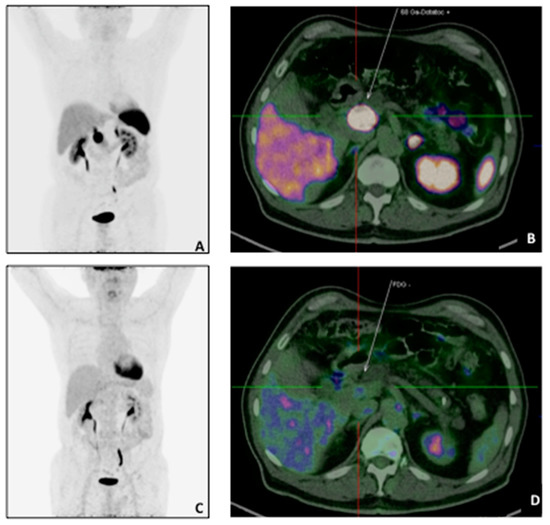

Among the 22 patients with a negative scan 12/22 (54.5%) had G1 (Ki67: 0.6% in 1/12, 1% in 10/12, 2% in 1/12) and 10/22 (45.4%) with G2 (Ki67: 3% in 1/10; 4% in 1/10, 5% in 3/10, 10% in 2/10, 17% in 1/10, 18% in 1/10, and 20% in 1/10) (Figure 1).

Figure 1.

A 73 years-old patient with pancreatic NET (G2, pT2N1M0) underwent 68Ga-DOTATATE and 18F-FDG PET/CT for staging purpose. The68Ga-DOTATATE MIP (A) and transaxial sections (B) showed intense uptake in correspondence of the primary tumour (white arrow: SUVmax: 107.1) with a negative 18F-FDG scan (MIP: (C); transaxial: (D).